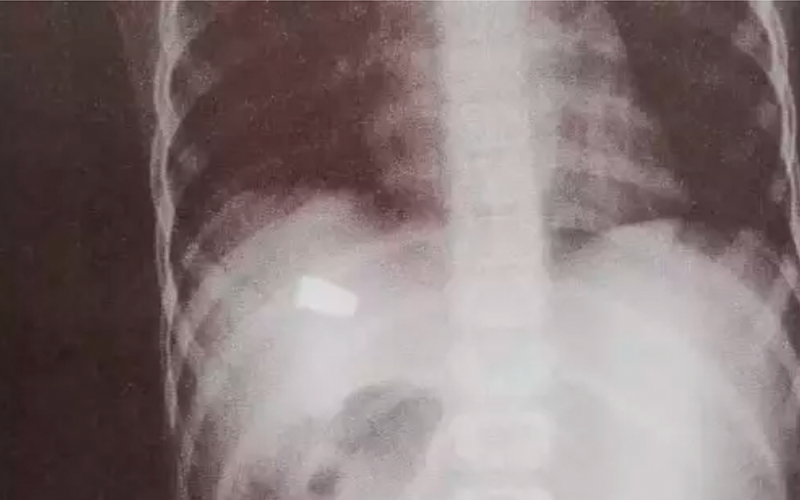

O menino disse à madrinha que sentiu dor no abdômen após ser atingido por um pedaço de telha da casa. Ao fazer um Raio X, foi constatado que a criança foi atingida por um tiro.

Na UPA, após realizar um exame de raio-x, os médicos identificaram que a lesão foi causada por um disparo de arma de fogo.